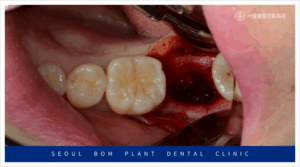

오금역치과 서울봄플란트에서는

아래턱 오른쪽 두 번째 어금니(#47)의 발치 후,

소파 작업을 철저히 진행하였습니다.

소파 작업은 임플란트 치료에서

매우 중요한 단계입니다.

만약 발치 후 염증 조직이 남아있을 경우,

잇몸뼈의 회복이 지연되고,

임플란트의 결합을 방해할 수 있습니다.

결국, 임플란트 주변에 다시 염증이

생길 위험이 있기 때문에,

꼼꼼한 소파 작업이 필수적입니다.